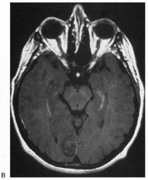

Fig. 5. Macula-splitting hemianopia. A 47-year-old man with AIDS and sudden onset of poor vision. A. Fields show complete left hemianopia. B. MRI shows lesion of right lateral occipital cortex, affecting distal optic radiations. Biopsy showed nonspecific encephalitis.